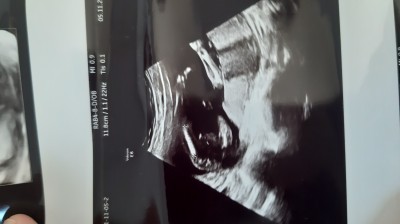

Kizlar doktor kız dedi bide baktımi bilen annelere sormak istedim

Gebelik haftası 16+3